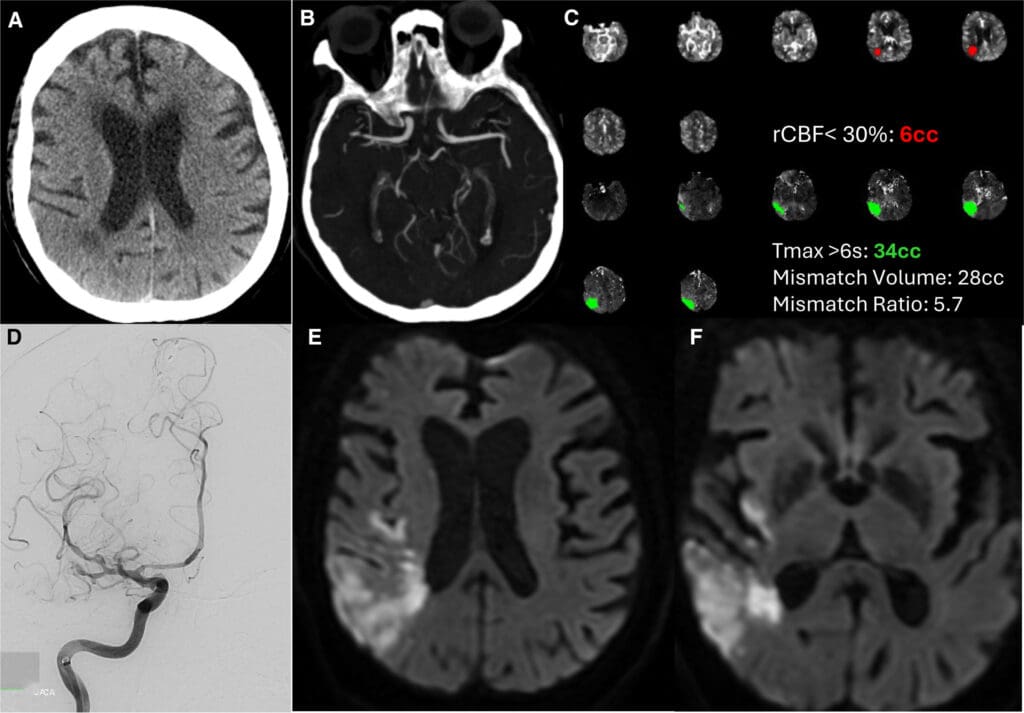

A 68-year-old woman with hypertension, hyperlipidemia, and poorly controlled type 2 diabetes (hemoglobin A1c, 13.8%) presented with acute left arm...